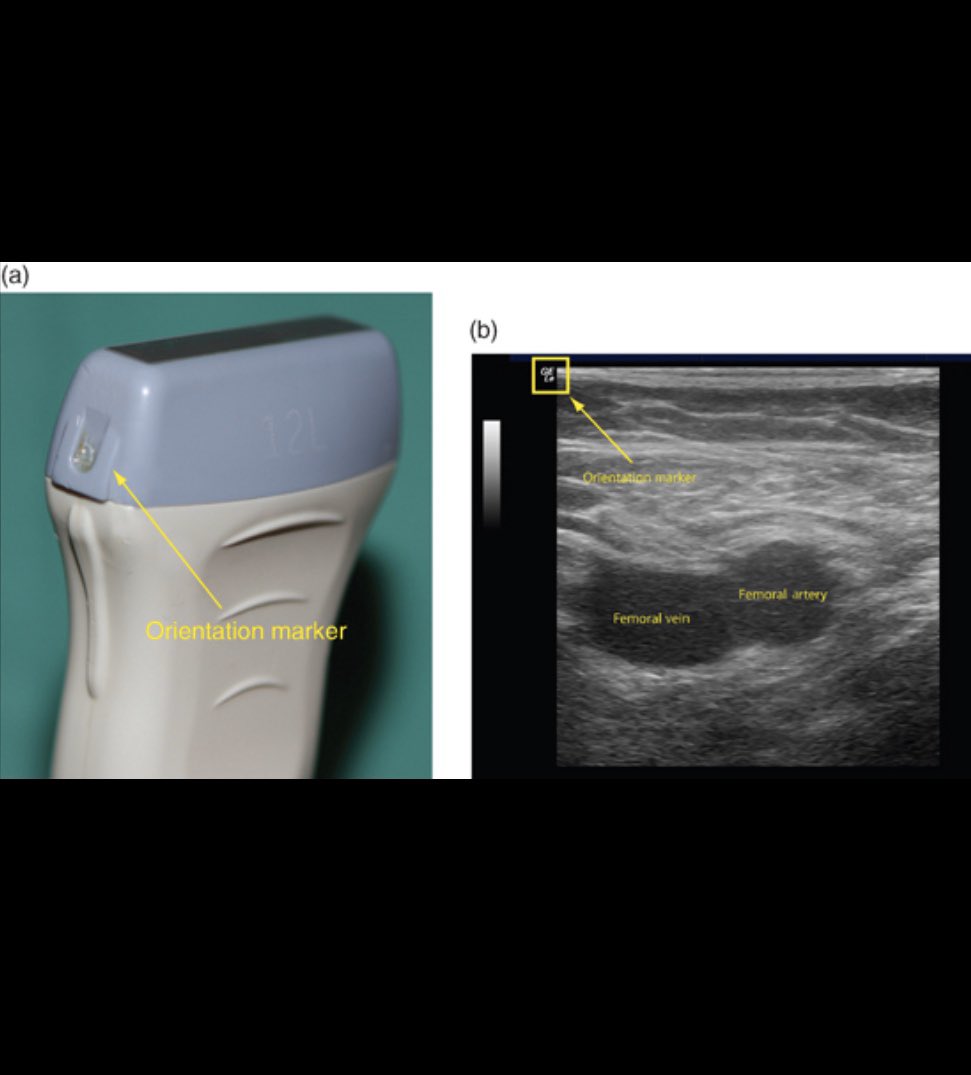

1 - notch or marker :

وهذي تكون على جنب البروب وفي حالات فحص الاوعيه وتدفقها لابد يكون اتجاه الmarker للرأس

وراح تشوفها برضوا بالشاشه فوق ولابد تكون يسار " بالشاشه " ويرمز لها برموز كثيره مثل (دائرة او كلمة Lugo) وهي تدل على مكان الرأس وهي مثل البوصلة الي تعلمنا وين الاتجاهات